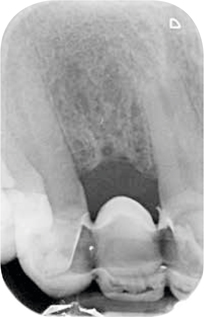

Röntgenonderzoek

Röntgenologisch onderzoek laat meerdere problemen zien. Onder andere een forse zwarting apicaal van element 12 met het beeld passend bij periapicale problematiek en een verleden van apicale chirurgie (afbeelding 8-12 ).

Afb. 9-10

Solo-opnamen van het 1e en 3e kwadrant.